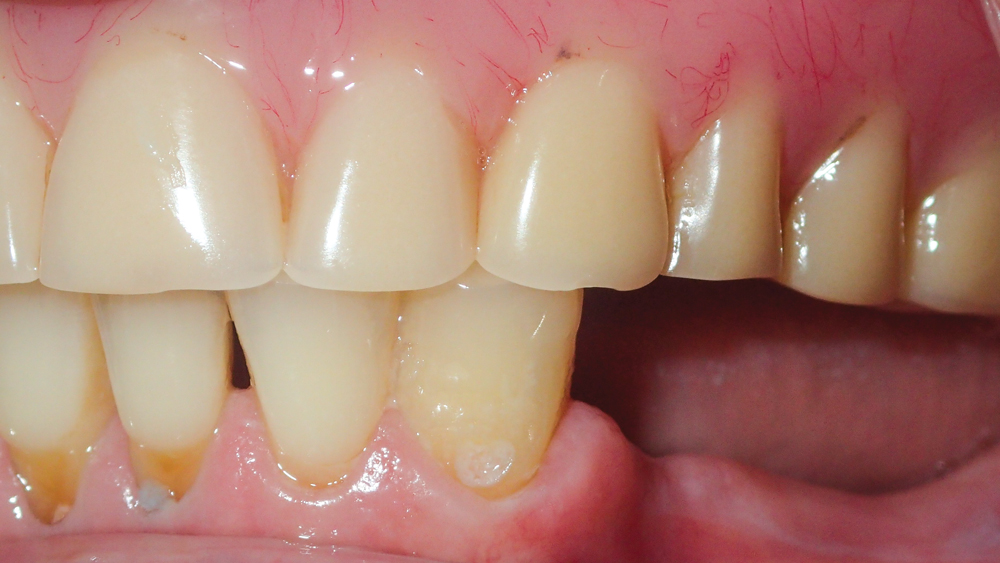

This patient was unhappy with the esthetics of her existing upper denture as well as the discomfort and instability caused by her loose-fitting mandibular partial denture. Although her concerns with the maxillary denture could be addressed with a new, more esthetic appliance, she preferred implant treatment for her mandible, where a fixed solution was needed to adequately restore function, stability and comfort.

The patient’s remaining mandibular teeth were extracted followed by immediate implant placement and delivery of a fixed provisional appliance. After integration of the implants, the prosthetic designs for the new upper denture and lower implant restoration were determined in tandem. Ultimately, the dual-arch restorations addressed the functional and esthetic challenges of the case while staying within the financial means of the patient, demonstrating the benefits of a flexible, multifaceted approach to restorative dentistry.